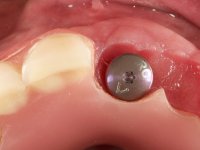

Primeira Fase

Foram feitas as extrações das raízes dos dentes 2.1 e 2.2 porque estavam a incomodar. Após 3 meses de cicatrização fez-se o exame imagiológico e estudo implantar para colocação do implante no local do 2.1.Foi colocado um implante de 4.1mm de diâmetro por 10mm de altura, colocado ao nível ósseo. Passados 2 meses após a cirurgia implantar, foi feita a segunda cirurgia para colocação de um parafuso de cicatrização. Foi feita a impressão ao implante com técnica de moldeira aberta com silicone de dupla viscosidade um mês após. No laboratório foi confecionada uma infraestrutura metálica para uma ponte de 2 elementos aparafusada ao implante. Esta infraestrutura apresentava 2 apoios palatinos para ajudar a estabilizar os dentes 1.1 e 2.3 a recuperar do traumatismo. Recuperados os dentes, os apoios poderiam ser retirados. Esta peça apresentava uma conexão interna ao implante com sistema anti-rotacional. A prova da infraestrutura foi feita em boca sendo o seu correto ajuste verificado com controle imagiológico. No revestimento da infraestrutura foi utilizada cerâmica de tonalidade coronária e gengival. Depois de verificada em boca e aprovada pelo paciente a ponte foi apertada definitivamente e o orifício de acesso obturado.